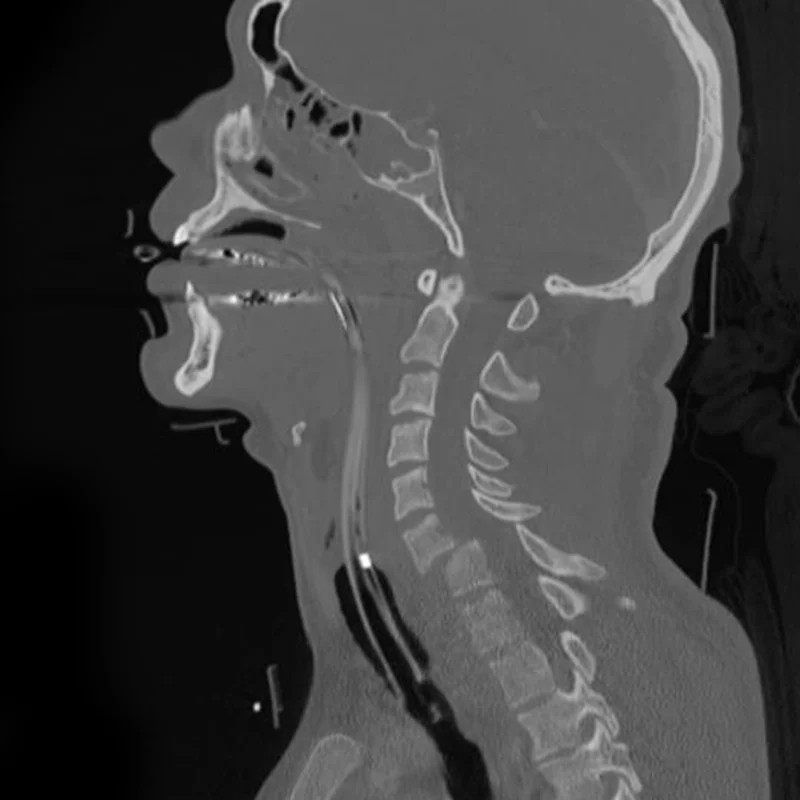

Diagnosis: why imaging matters more than symptoms

Cervical fracture spine Xray

Photo- Wikimedia Commons

Cervical fractures are frequently underdiagnosed if only clinical symptoms are considered.

X-ray

Useful but may miss subtle injuries

CT scan

Gold standard for bone assessment

MRI

Essential when:

• neurological symptoms are present

• ligament injury is suspected

Recent advances also include AI-based detection systems that improve fracture identification accuracy. (Singh et al. 2025)

AI-assisted tools are being developed to support early and accurate diagnosis.